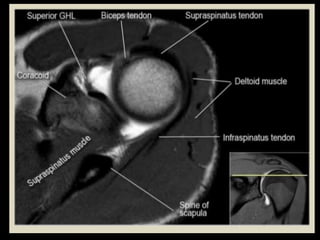

Shoulder